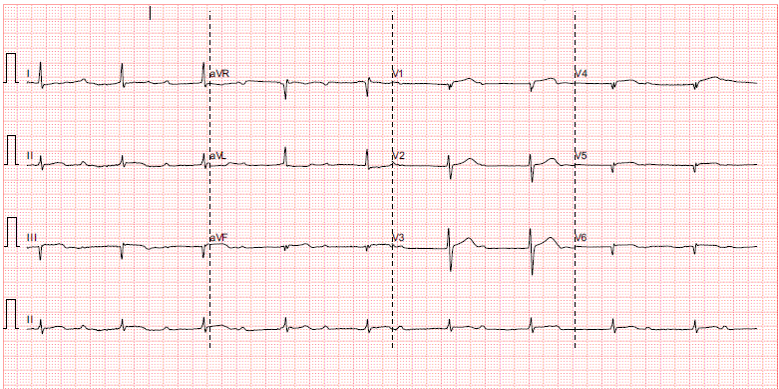

Mr A is a 45 year old construction site worker with unremarkable past health. He is active smoker with 30 pack years. He has no family history of premature CAD. He presented with sudden onset of severe chest pain at 1am. Prehospital ECG showed complete heart block, 50 beats per min, ST segment elevation at inferior leads with right side involvement.

His vitals are stable: BP 160/116 P53 SpO2 98% RA Hstix 15

Bloods tests are grossly unremarkable. Troponin 218 (<= 34.2) CK 412

CXR is clear

Echo shows impaired LV systolic function, EF ~ 45%, inferior wall hypokinesia. Dilated RV Mild MR. no AR. mod TR. No pericardial effusion.PPCI is activated. He is sent to catherization lab immediately.